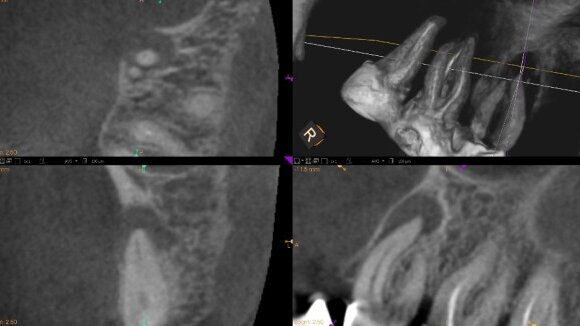

Zdecydowano o poszerzeniu diagnostyki o tomografię komputerową (Ryc. 9). Na przekrojach strzałkowych widać ubytek osteolityczny odpowiadający przewlekłemu zapaleniu tkanek okołowierzchołkowych sięgający od wierzchołka korzenia mezjalnego policzkowego zęba 16 do furkacji. Po wnikliwej analizie CBCT stwierdzono niedostateczne opracowanie kanału mezjalno-policzkowego pierwszego (MB1) oraz obecność kanału MB2, którego uprzednio nie odnaleziono i nie opracowano. Blaszka kostna od strony podniebiennej była nienaruszona. Przypuszczano, że zmiana łączona endo-perio prawdopodobnie miała etiologię endodontyczną.

Na podstawie tych informacji oraz po rozmowie z pacjentką podjęto próbę leczenia kanałowego. W tym celu odbudowano ząb do ubytku pierwszej klasy wg Blacka i wykonano jednoseansowe leczenie endodontyczne w osłonie koferdamu, które zostało zakończone cementowaniem włókien szklanych. Po 9 miesiącach wykonano tomografię kontrolną (Ryc. 10). Na kontrolnym CBCT stwierdzono całkowite wypełnienie furkacji kością gąbczastą. Na zębie została wykonana praca protetyczna w postaci korony porcelanowej na podbudowie metalowej.